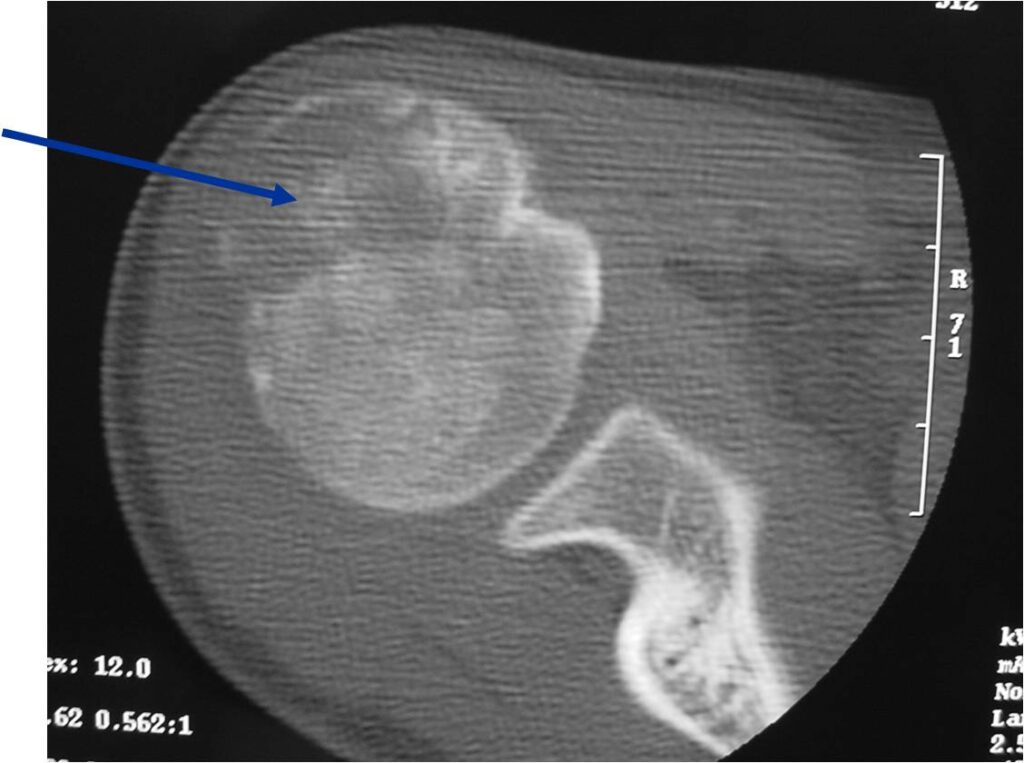

- (CT appearance)

- Most useful for detecting subtle mineralization not apparent on X-rays

- Useful for identifying intact periosteum around any expansile soft tissue component

- surrounding thin reactive shell of bone/mineralization (Egg Shell Rim of Calcification)

- helps place the tumor in a benign category

- helps evaluate:

- bony quality

- extent of bone and cortical destruction

- whether the subchondral plate of bone adjacent to the articular cartilage has been destroyed or is intact